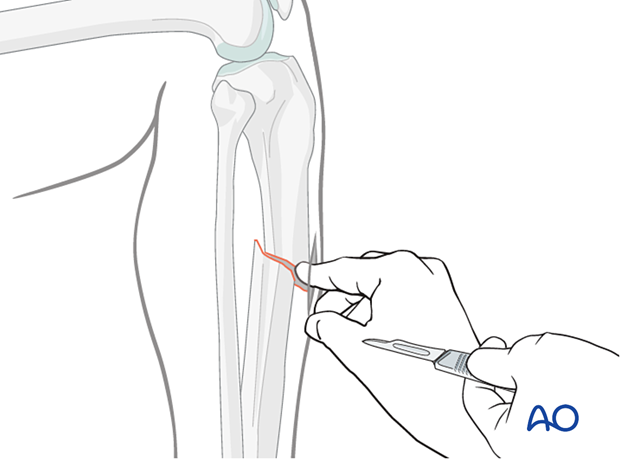

To aid reduction, a “joystick” (in this case a Schanz screw on a T-handled chuck) can be placed percutaneously into either or both main tibial fragments. The Schanz screw should have unicortical purchase so that it does not block the guide wire, reamer, or nail.

Oblique or spiral fractures can often be reduced with pointed reduction forceps applied percutaneously.